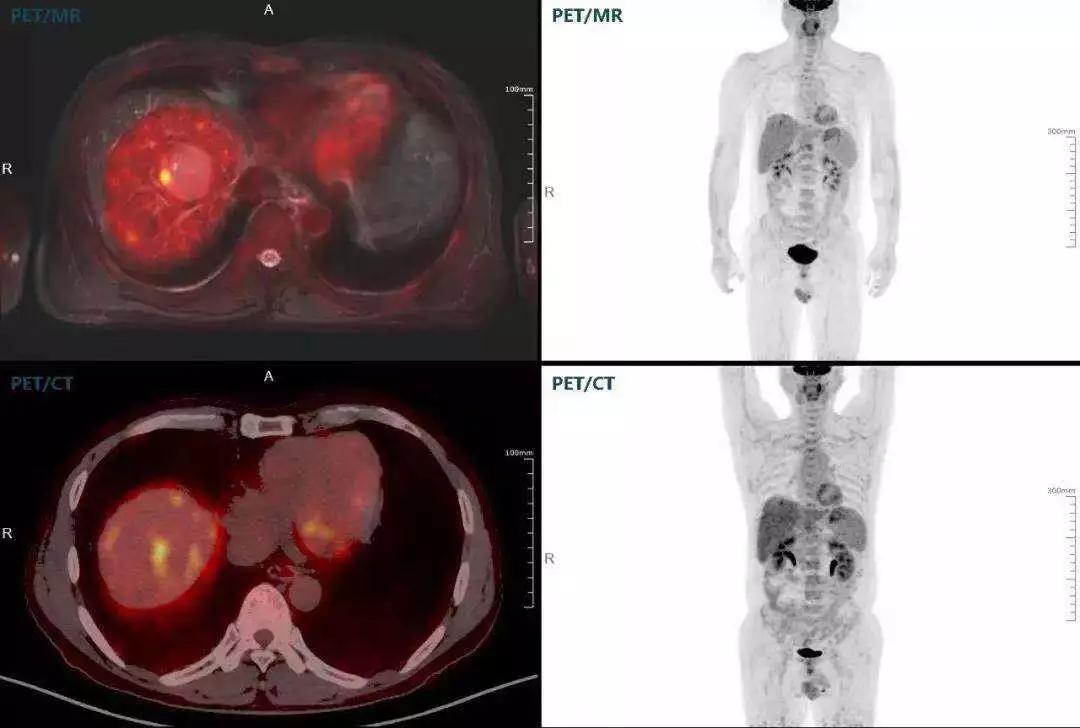

肝癌

聯(lián)影“時空一體”超清TOF PET/MR搭載的壓縮感知技術(shù),能夠同時實現(xiàn)16期成像,精準(zhǔn)捕獲肝臟動態(tài)影像的每一瞬間,同時兼顧早期與晚期等全部期相的完整病灶信息,實時、全方位鎖定病灶。同時,基于其2.8mm超高分辨率,能夠精細(xì)呈現(xiàn)腫瘤邊界信息,捕捉局部微小病灶與遠(yuǎn)端轉(zhuǎn)移灶,助力醫(yī)生精準(zhǔn)診斷。

(對于同一例肝臟惡性腫瘤,PET-CT與PET/MR成像對比。可以看到,聯(lián)影PET/MR圖像對腫瘤邊界和FDG高濃聚區(qū)域清晰顯示。)